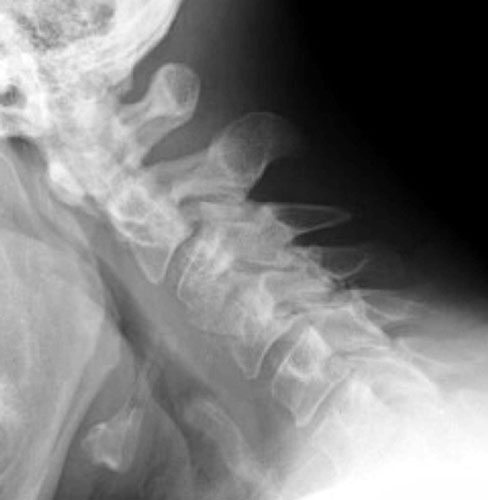

48 y.o. male with a history of alcohol abuse, depression and degenerative

joint disease who is complaining of severe pain in his right neck and shoulder

radiating down to his right third and fourth digit. The patient underwent

anterior cervical disc fusion. Four months after the initial surgery, the

patient still had pain but this time numbness was on flexion mainly and

localized to the C5 region.

Lateral flexion and extension radiographs taken 6 months after

surgery demonstrate incomplete graft incorporation (delayed healing).

Furthermore, with flexion there is anterolisthesis of C4 on C5 (one level below

the fusion) by 2-3 mm.